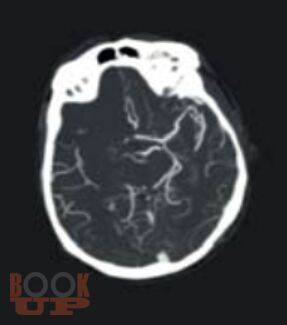

Руководство стандартизирует подходы к диагностике, лечению, реабилитации и вторичной профилактике ишемического инсульта. Изложение построено в соответствии с реальной логикой ведения пациента: от дефиниций и дифференциальной диагностики с имитаторами, через патогенетические подтипы, экстренную нейровизуализацию, реперфузионную и базисную терапию, раннюю реабилитацию, до поиска причины инсульта и вторичной профилактики.

Материал представлен в компактной форме с использованием схем, таблиц, алгоритмов и клинических примеров. Отдельные разделы посвящены инсульту у беременных и церебральному венозному тромбозу.